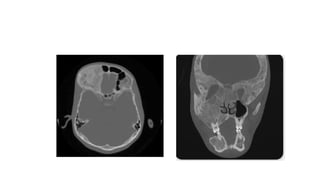

• CT demonstrates the classical feature of a round or oval nidus of soft

tissue density which commonly shows central dense mineralisation

• CT demonstratesthe classical feature of a round or oval nidus of soft tissue density which commonly shows central dense mineralisation